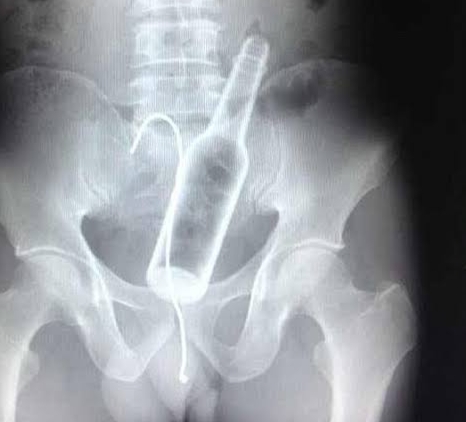

ನಡೆದ ಘಟನೆ ಏನೆಂದರೆ ಒಬ್ಬ ಯುವಕನು ಹೊಟ್ಟೆಯಲ್ಲಿ ತುಂಬಾ ನೋವಾಗುತ್ತಿರುವದರಿಂದ ಆತನು ನಾಗಪಟ್ಟಿನಂ ಆಸ್ಪತ್ರೆಯಲ್ಲಿ ಚಿಕಿತ್ಸೆ ಪಡೆಯಲು ಹೋದನು. ಆತನ ಪ್ರಾಥಮಿಕ ತಪಾಸಣೆ ಮಾಡಿದಾಗ ಅಲ್ಲಿದ್ದ ವೈದ್ಯರು ಹೊಟ್ಟೆಯಲ್ಲಿ ಏನೋ ಇದ್ದಿರಬಹುದು ಎಂದು ಯುವಕನಿಗೆ ತಿಳಿಸಿದರು. ತದನಂತರ ಡಾಕ್ಟರ್ ಆತನನ್ನು ಸಿಟಿ ಸ್ಕ್ಯಾನಿಂಗ್ ಮಾಡಿಕೊಳ್ಳಲು ತಿಳಿಸಿದರು. ಸ್ಕ್ಯಾನಿಂಗ್ ಮಾಡಿದ ಮೇಲೆ ಬಂದ ರಿಪೋರ್ಟ್ ನೋಡಿ ಡಾಕ್ಟರ್ ಸಹ ಆಶ್ಚರ್ಯಗೊಂಡರು. ಏಕೆಂದರೆ ರಿಪೋರ್ಟ್ ನಲ್ಲಿ ಯುವಕನ ಹೊಟ್ಟೆಯಲ್ಲಿ ಗಾಜಿನ ಬಾಟಲಿ ಇದೆಯಂದು ತಿಳಿದು ಬಂದಿತು.

ಮರುದಿನ ಆ ಯುವಕನ ಮೇಲೆ ಸುಮಾರು 2 ಗಂಟೆಯ ವರೆಗೆ ಚಿಕಿತ್ಸೆ ನಡೆಸಿ ಅವನ ಹೊಟ್ಟೆಯಲ್ಲಿದ್ದ ಗಾಜಿನ ಬಾಟಲಿಯನ್ನು ಹೊರಗಡೆ ತಗೆದರು. ಈ ವಿಚಿತ್ರ ಘಟನೆಯ ಬಗ್ಗೆ ಅಂದರೆ ಹೊಟ್ಟೆಯಲ್ಲಿ ಗಾಜಿನ ಬಾಟಲ್ ಹೇಗೆ ಬಂತು ಅಂತ ಯುವಕನನ್ನು ಕೇಳಿದಾಗ, ” ಮದ್ಯದ ಅಮಲಿನಲ್ಲಿದ್ದಾಗ ನನ್ನ ಗುದದ್ವಾರದ ಮುಖಾಂತರ ನಾನು ಈ ಬಾಟಲಿಯನ್ನು ಒಳಗೆ ಹಾಕಿಕೊಂಡಿದ್ದೇನೆ ” ಎಂದು ಹೇಳಿದನು. ಇದನ್ನು ಕೇಳಿ ಡಾಕ್ಟರ್ ಸಹ ನಿಬ್ಬೆರಗಾದರು.